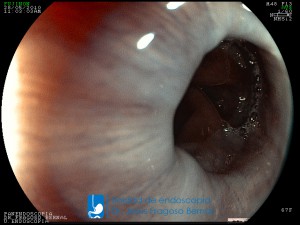

La Unidad de Endoscopía fue creada en 2002 por el Dr. Jesús Fragoso Bernal, es pionera en el estado por la utilización de la tecnología más avanzada, que nos permite ofrecer servicios integrales de diagnóstico y tratamiento para las enfermedades del aparato digestivo.